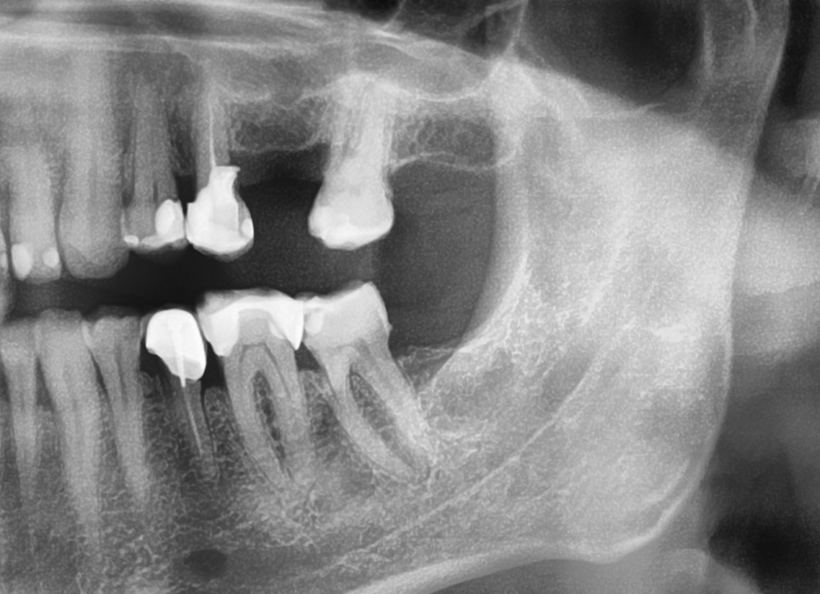

Radiografia digitală panoramică sau Ortopantomografia este radiografia digitală care ne oferă o imagine de ansamblu la toţi dinţii din cavitatea bucală, inclusiv sinusurile maxilare şi aticulaţiile temporo-mandibulare. Este indicată la începerea unui tratament stomatologic pentru a vedea zonele mai greu accesibile ale dinţilori, retracţiile osoase, existenţa şi adâncimea pungilor parodontale, existenţa dinţilor incluşi, etc.

Radiografia digitală panoramică O.P.T. pentru sinusurile maxilare